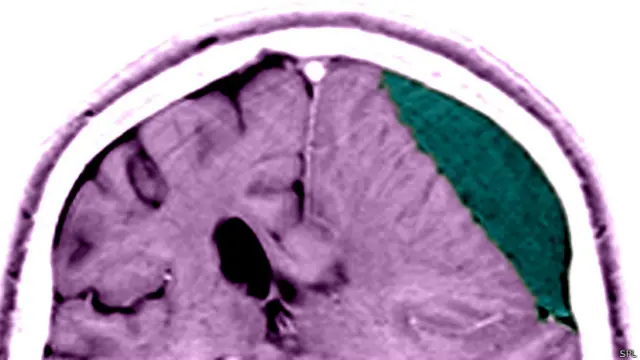

Beyin ameliyatında üç boyutlu yöntem

Birkaç yıl önce de 3D, yani üç boyutlu beyin ameliyatı yapmanın yöntemini geliştiriyor.

Çünkü nöroşirürjide beyne uzatılan kameranın çapının burun gibi dar noktalardan geçebilecek kadar küçük olması gerekir.

Beyin cerrahlarının ihtiyacı olan yüksek kalitede görüntüler üretmek için yeterli güçte bir enstrümanı o kadar küçük boyutta imal etmenin de zor olduğu düşünülüyordu.

Ama Yaron ve ekibi bu bulmacayı çözdüklerini söylüyorlar.

İnsan anatomisini kopyalamak yerine geliştirdikleri enstrüman bir arı gözünü taklit ediyor.

Bir yazılım kullanarak veriler sol ve sağ göz için görüntülere çevriliyor.

Yaron'nun şirketi Visionsense, tek bir sensör sistemi kullanarak beyin üzerinde çalıştırmak için yeterince küçük bir kamera üretti.

Ayrıca bu şekilde cerrahın aletlerini de üç boyutlu görmek mümkün...

Bu da ameliyat aletlerinin vücudun neresinde olduğunun daha iyi anlamalarını sağlıyor.